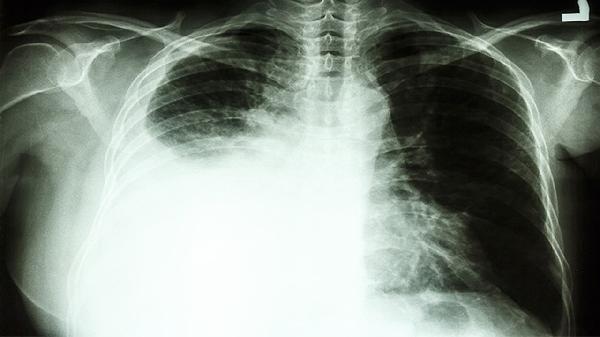

首先可以明确的告诉你,腹主动脉夹层破裂在临床上属于非常非常危险的急症,必须急诊手术开刀治疗,延误病情者死亡率极高。必须立刻、马上手术治疗。而且手术费用往往不低,具体的手术费用需要根据临床的病情程度、医院的等级水平、当地的物价水平等因素综合决定。一般来说都是10万左右。有条件的话到正规医院做个检查,排除有其他疾病可能性。